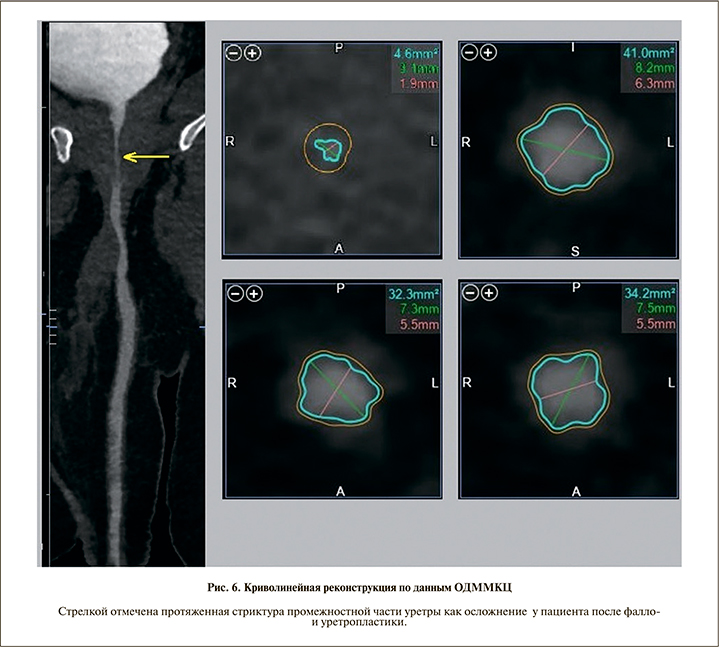

Все полученные изображения были обработаны на рабочей станции Vitrea с построением криволинейных реконструкций уретры и автоматическим определением ее диаметра во всех отделах (рис. 6). Средний диаметр уретры, по данным ОДММКЦ, после выполнения уретропластики составил 7,6±2,1 мм. Минимальная протяженность стриктур уретры составила 17, максимальная – 32 мм.

Результаты. При анализе полученных данных всех пациентов были установлены причина и локализация стриктуры уретры (см. рис. 1) или иной патологии (см. рис. 2).